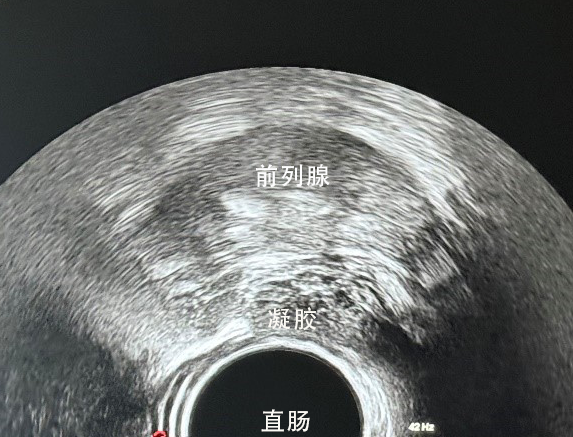

治疗过程创新采用超声实时引导+凝胶隔离防护技术:

1.精准定位:在超声可视化引导下,将穿刺针精准置入前列腺与直肠之间的筋膜间隙;

2.形成屏障:注入专用防护凝胶,均匀扩散形成稳定物理隔离层;

3.有效分离:显著增加前列腺与直肠间距,大幅降低直肠受照剂量;

1.术中超声清晰显示:凝胶均匀扩散,分隔效果理想;